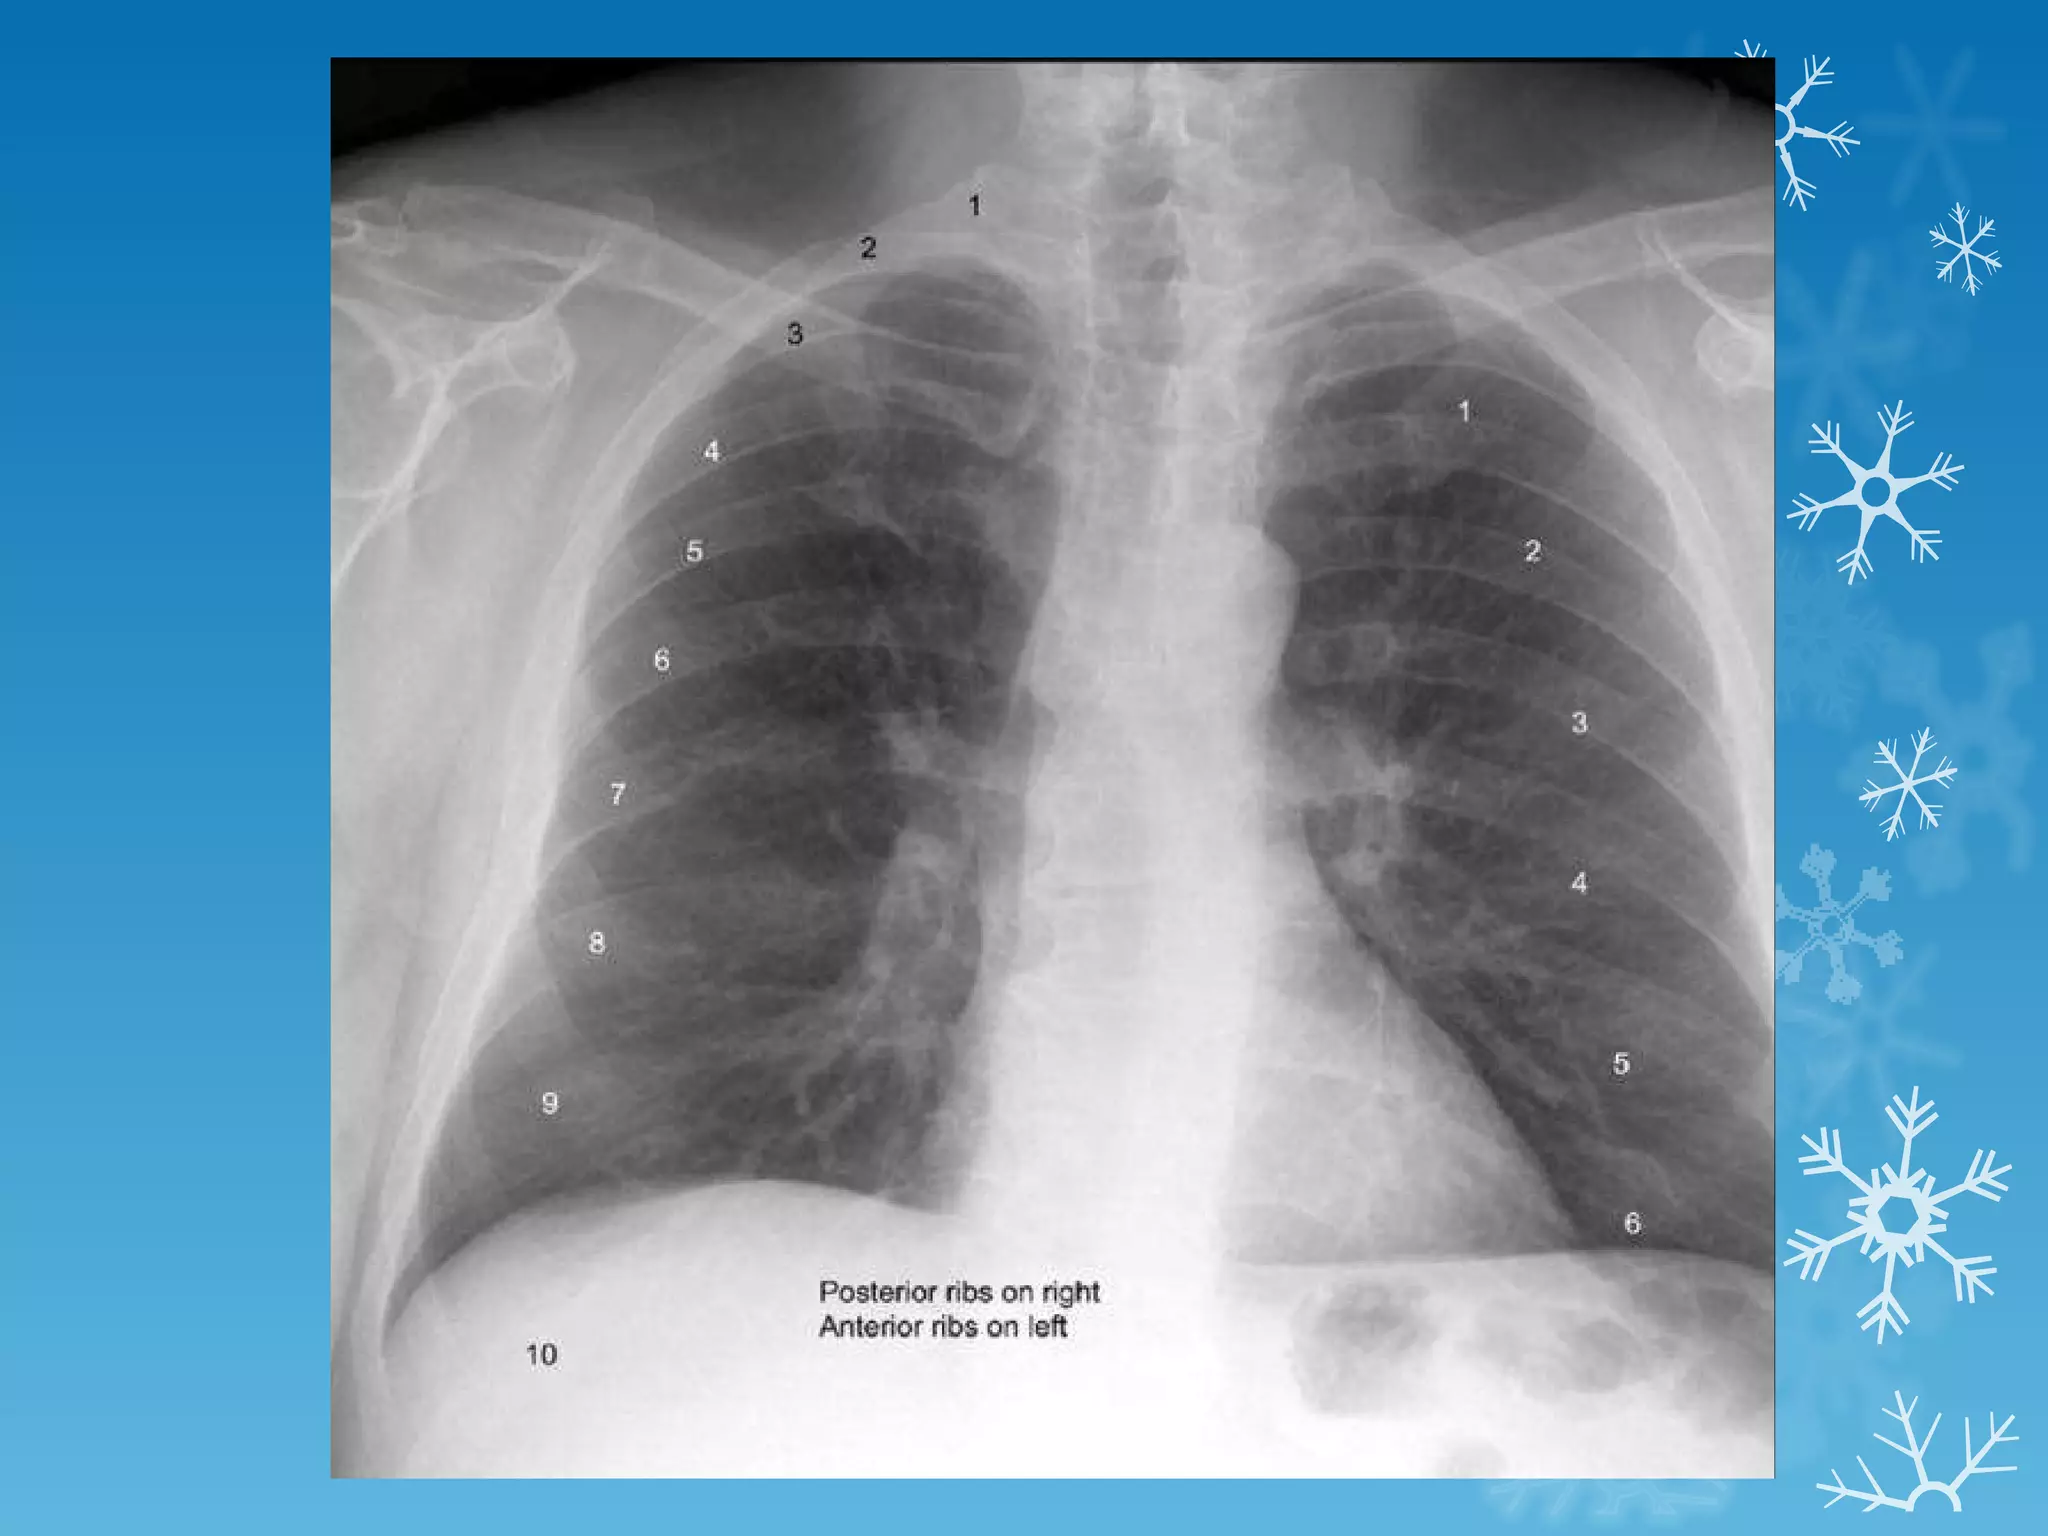

This document discusses chest x-ray interpretation and provides guidance on evaluating x-rays. It explains that tissue density determines how an x-ray beam penetrates, with denser tissues appearing whiter and less dense tissues appearing blacker. It also outlines different chest x-ray views and factors to consider like patient orientation, age, gender, and rotation. Abnormalities are described as appearing too white, too black, too large, or in the wrong place. The document stresses a systematic approach of identifying, localizing, describing lesions, and providing differential diagnoses.